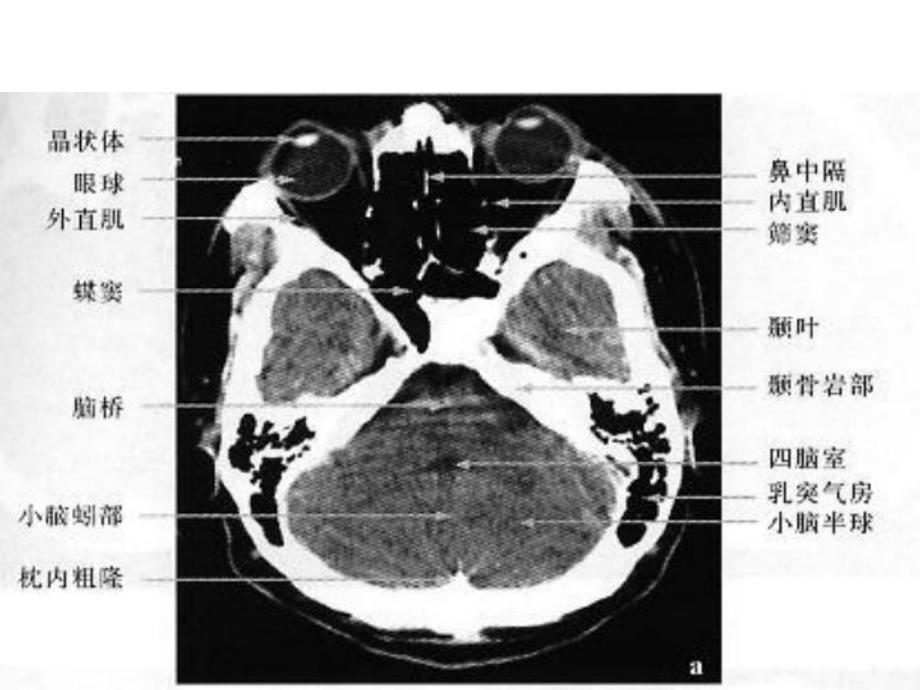

颅脑、解剖 硬膜外血肿 硬膜下血肿 蛛网膜下腔出血 脑挫裂伤 脑积水(交通性、阻塞性)(正压、负压)(占位效应)